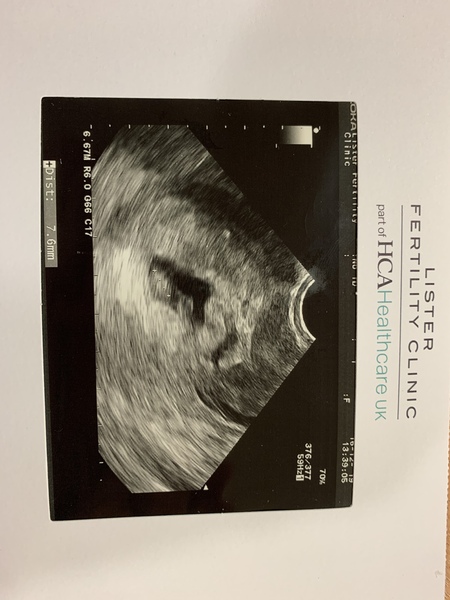

Jojo19834 · 16/12/2019 20:24

Here’s mine, I’m calling it the blob at the moment. Inside the black area you can see baby blob at the bottom and sac blob at the top!